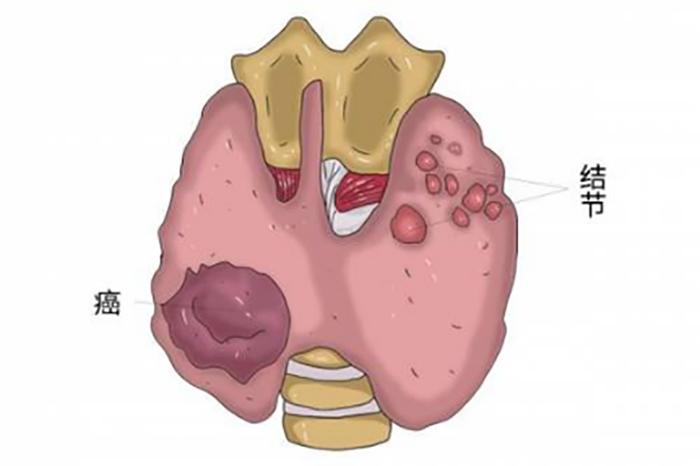

甲状腺结节是甲状腺细胞的异常生长产生的“肿块”,可能是单个,也可能是多个。

绝大多数情况下,超过90%的甲状腺结节是良性的,只有5%-15%的甲状腺结节为恶性,即甲状腺癌。